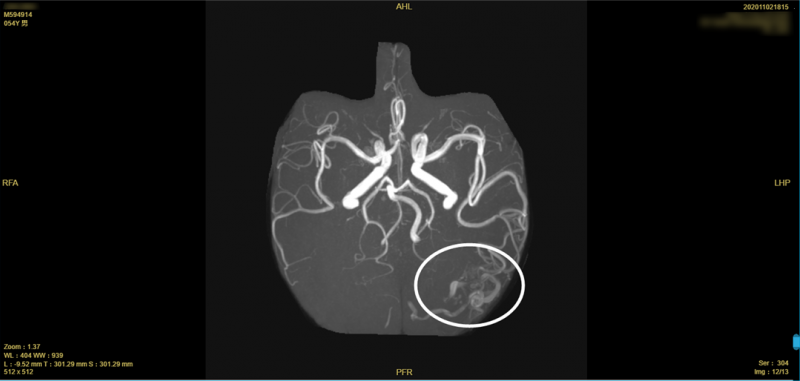

图中所示为患者的“颅内炸弹”。

脑动静脉畸形属先天性血管发育异常导致的疾病,是脑内血管发育过程中残留的一些未闭塞的异常血管随着时间推移而形成的畸形血管团。其血管壁很脆,易破裂,容易引发颅内出血,因此被称为“颅内炸弹”。一旦“颅内炸弹”在颅内“引爆”,患者轻则失语、肢体偏瘫,重则危及生命。此前,田先生已经遇到过两次颅内出血,再次出血的几率极高,一旦血管再次破裂,或将带来不堪设想的后果。